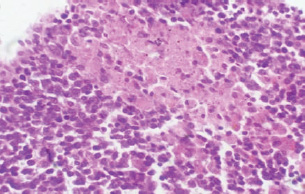

At 21 days post-infection, the lungs display moderate venous dilation and congestion, with abnormal leukocytes, indicating ongoing vascular compromise (Fig. 9). The liver showed necrotic changes in the fibrous capsule region, focal inflammatory cell infiltration, and intact hepatic cords, indicating sustained but localized damage (Fig. 10). The spleen exhibited plasma cell and macrophage proliferation within the red pulp, mild sinus dilation, and a few megakaryocytes, suggesting chronic immune activation (Fig. 11). The kidneys showed atrophic glomerular tufts and cystic dilation of adjacent tubules, indicating worsening renal pathology (Fig. 12). The mesenteric lymph nodes showed lymphoid follicles containing abnormal plasma cells and macrophages within the necrotic foci (Fig. 13).

Fig. 11. A histopathological section of the spleen (G2) at 21 days postinfection showing the main splenic findings characterized by proliferation of the plasma cell and macrophages within red pulp tissue with mild sinus dilation and few megakaryocytes (H&E stain X 40).

Fig. 13. A histopathological section of the mesenteric lymph node of (G2) at 21 days postinfection showing a lymphoid follicle containing numbers of abnormal plasma cells and macrophages within necrotic foci (H&E stain X 40).